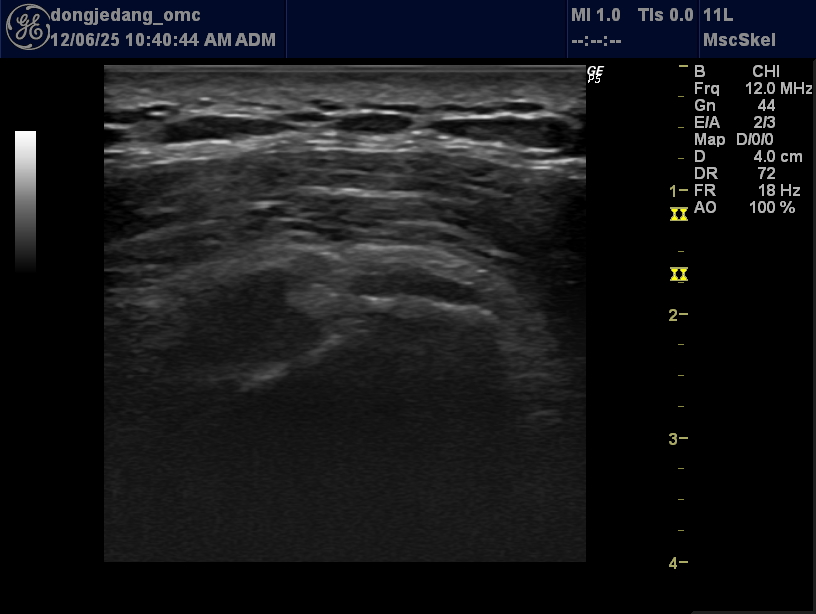

초음파 이미지

• 대퇴골 관절면의 경미한 피질 불규칙성(Cortical irregularity) 초자연골(Hyaline cartilage) 두께의 전반적 보존 및 국소적 경계면 모호 뚜렷한 거대 골극(Osteophyte) 형성이나 연골하 낭종(Subchondral cyst) 부재 관절강 내 유의미한 삼출액(Joint effusion) 저류 관찰되지 않음 우슬 초기 퇴행성 관절염(Early Degenerative Osteoarthritis) 소견 임상적 중증도 분류(Kellgren-Lawrence Grade) 추정 시 Grade 1 (미세한 골극 형성 가능성 및 관절 간격의 변화가 의심되나 확정적이지 않은 상태)에 해당할 가능성이 높음. 46세 남성임을 고려할 때 연령 증가에 따른 자연스러운 초기 변화와 병적 변화의 경계선상에 있는 것으로 사료됨.